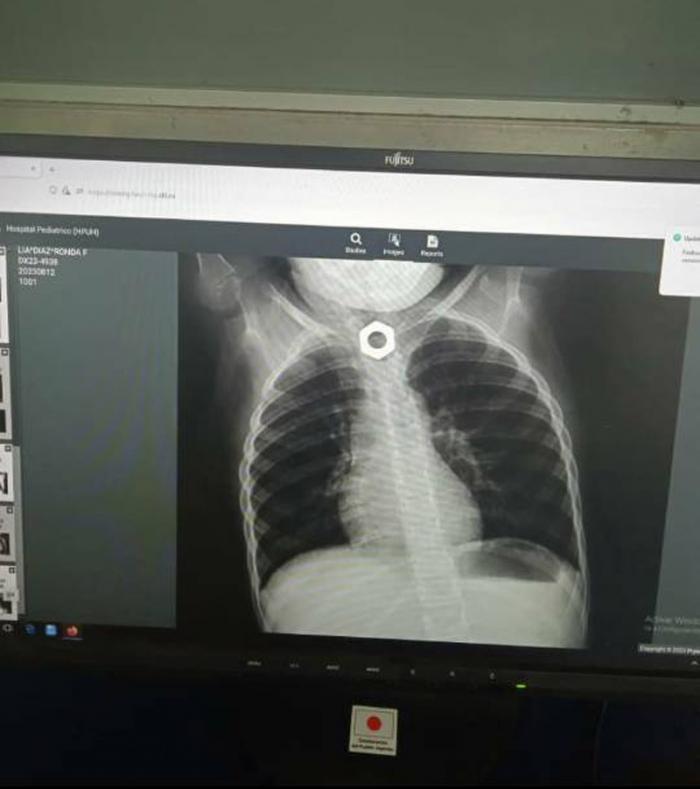

Allí la recibió el doctor Alberto Ibarra Batista, especialista en Otorrinolaringología, que se encontraba de guarda médica localizable, a la llegada de la niña se le indicó un nuevo estudio radiográfico y de inmediato la entraron salón de operaciones para realizarle una esofagoscopia bajo anestesia general y extraer la tuerca. El doctor contó que el proceder resultó bastante trabajoso, pero sin mayores complicaciones.

«El esófago de la paciente estaba muy traumatizado, pero sin perforación, por lo cual se le colocó, bajo visión endoscópica, una sonda nasogástrica para dar reposo al tubo muscular que transporta los alimentos y líquidos desde la boca hasta el estómago», agregó el especialista que estuvo acompañado en la cirugía por la anestesióloga Moraima Gendis; el doctor Oscar López y el cirujano Adrián Ramírez. A la paciente le fue retirada ya la sonda y tolera la dieta líquida sin mayores problemas.